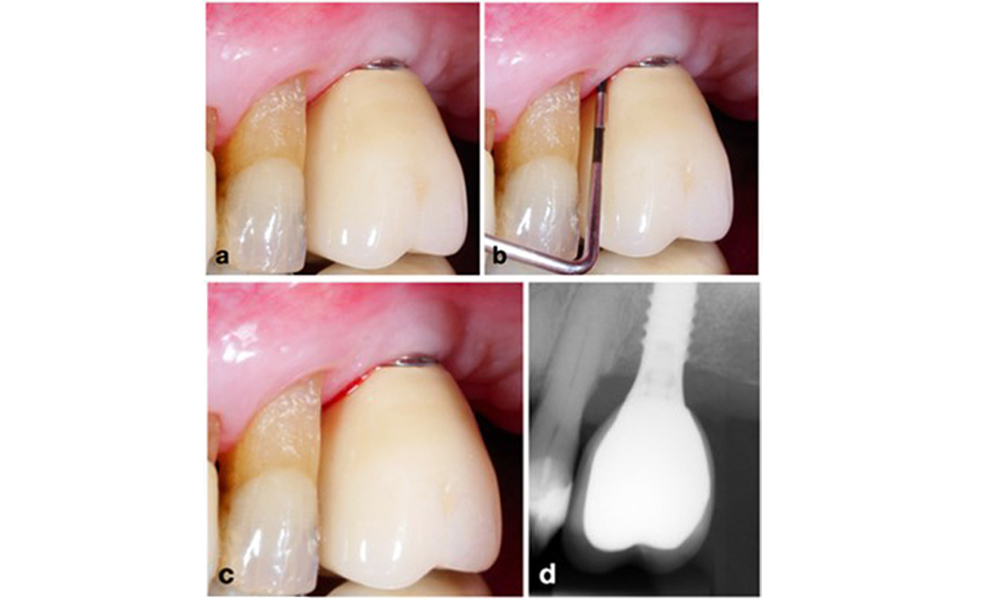

Le World Workshop on the Classification of Periodontal and Peri-Implant Diseases and Conditions de 2017 a établi des critères de diagnostic pour la mucosite péri-implantaire et la péri-implantite (Renvert et al. 2018). La mucosite péri-implantaire est définie comme (1) la présence d'une inflammation autour de l'implant (c'est-à-dire une rougeur, un gonflement, une ligne ou une goutte de saignement dans les 30 secondes suivant le sondage), associée à (2) l'absence de perte osseuse supplémentaire après la cicatrisation initiale (figure 1).

Implant en position 26 avec mucosite péri-implantaire (a-c). La valeur de la profondeur de sondage de 5 mm (b) reste cohérente avec la mesure prise quelques semaines après la mise en place de la reconstruction prothétique. Il y a un saignement au sondage (c) mais la radiographie n'indique pas de perte osseuse supplémentaire au-delà de ce qui est attendu pour un remodelage de l'os marginal (d).

Figure 1. Implant en position 26 avec mucosite péri-implantaire (a-c). La valeur de la profondeur de sondage de 5 mm (b) reste cohérente avec la mesure prise quelques semaines après la mise en place de la reconstruction prothétique. Il y a un saignement au sondage (c) mais la radiographie n'indique pas de perte osseuse supplémentaire au-delà de ce qui est attendu pour un remodelage de l'os marginal (d).